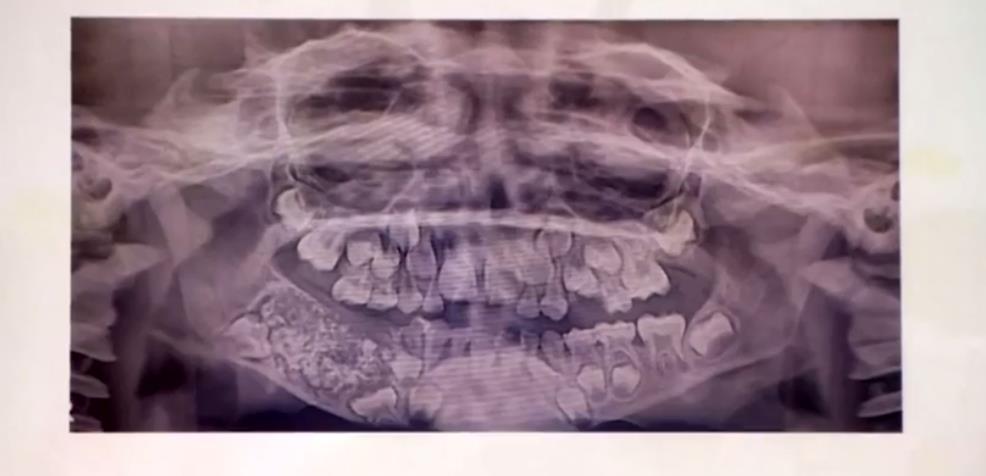

وأظهر فحص طبي أجراه جراحون، وجود نمو كبير يحتوي على هياكل صلبة متعددة في الفك.

وقال الأطباء إن هذه حالة طبية فريدة من نوعها. ووصفت الحالة النادرة بأنها "ورم مركب بالأسنان".